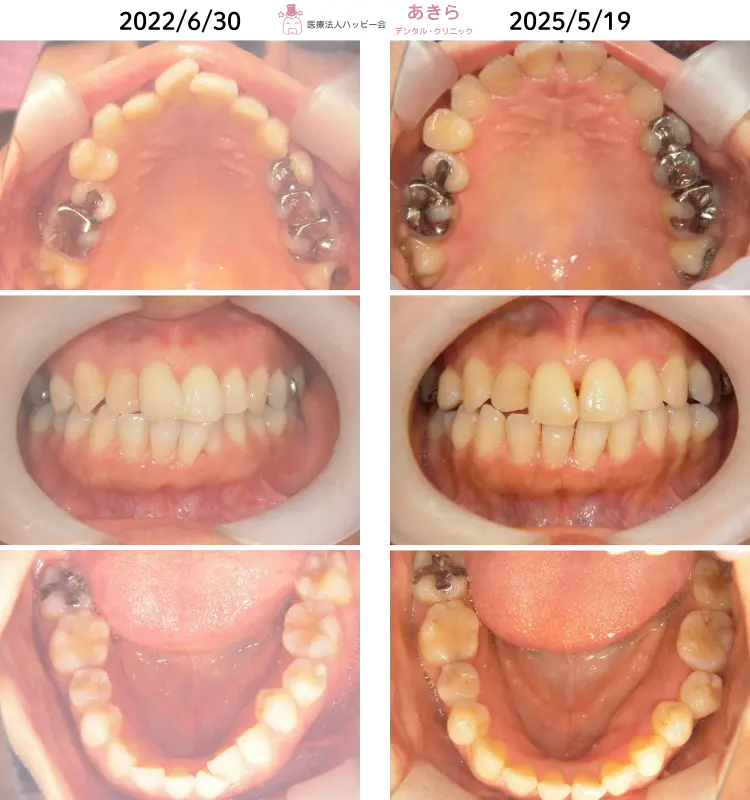

SH療法

SH療法-症例-No.012-外傷歯を伴う叢生(凸凹)の矯正症例

山形市の歯医者「あきらデンタル・クリニック」のSH療法の症例をご紹介します。 SH… -